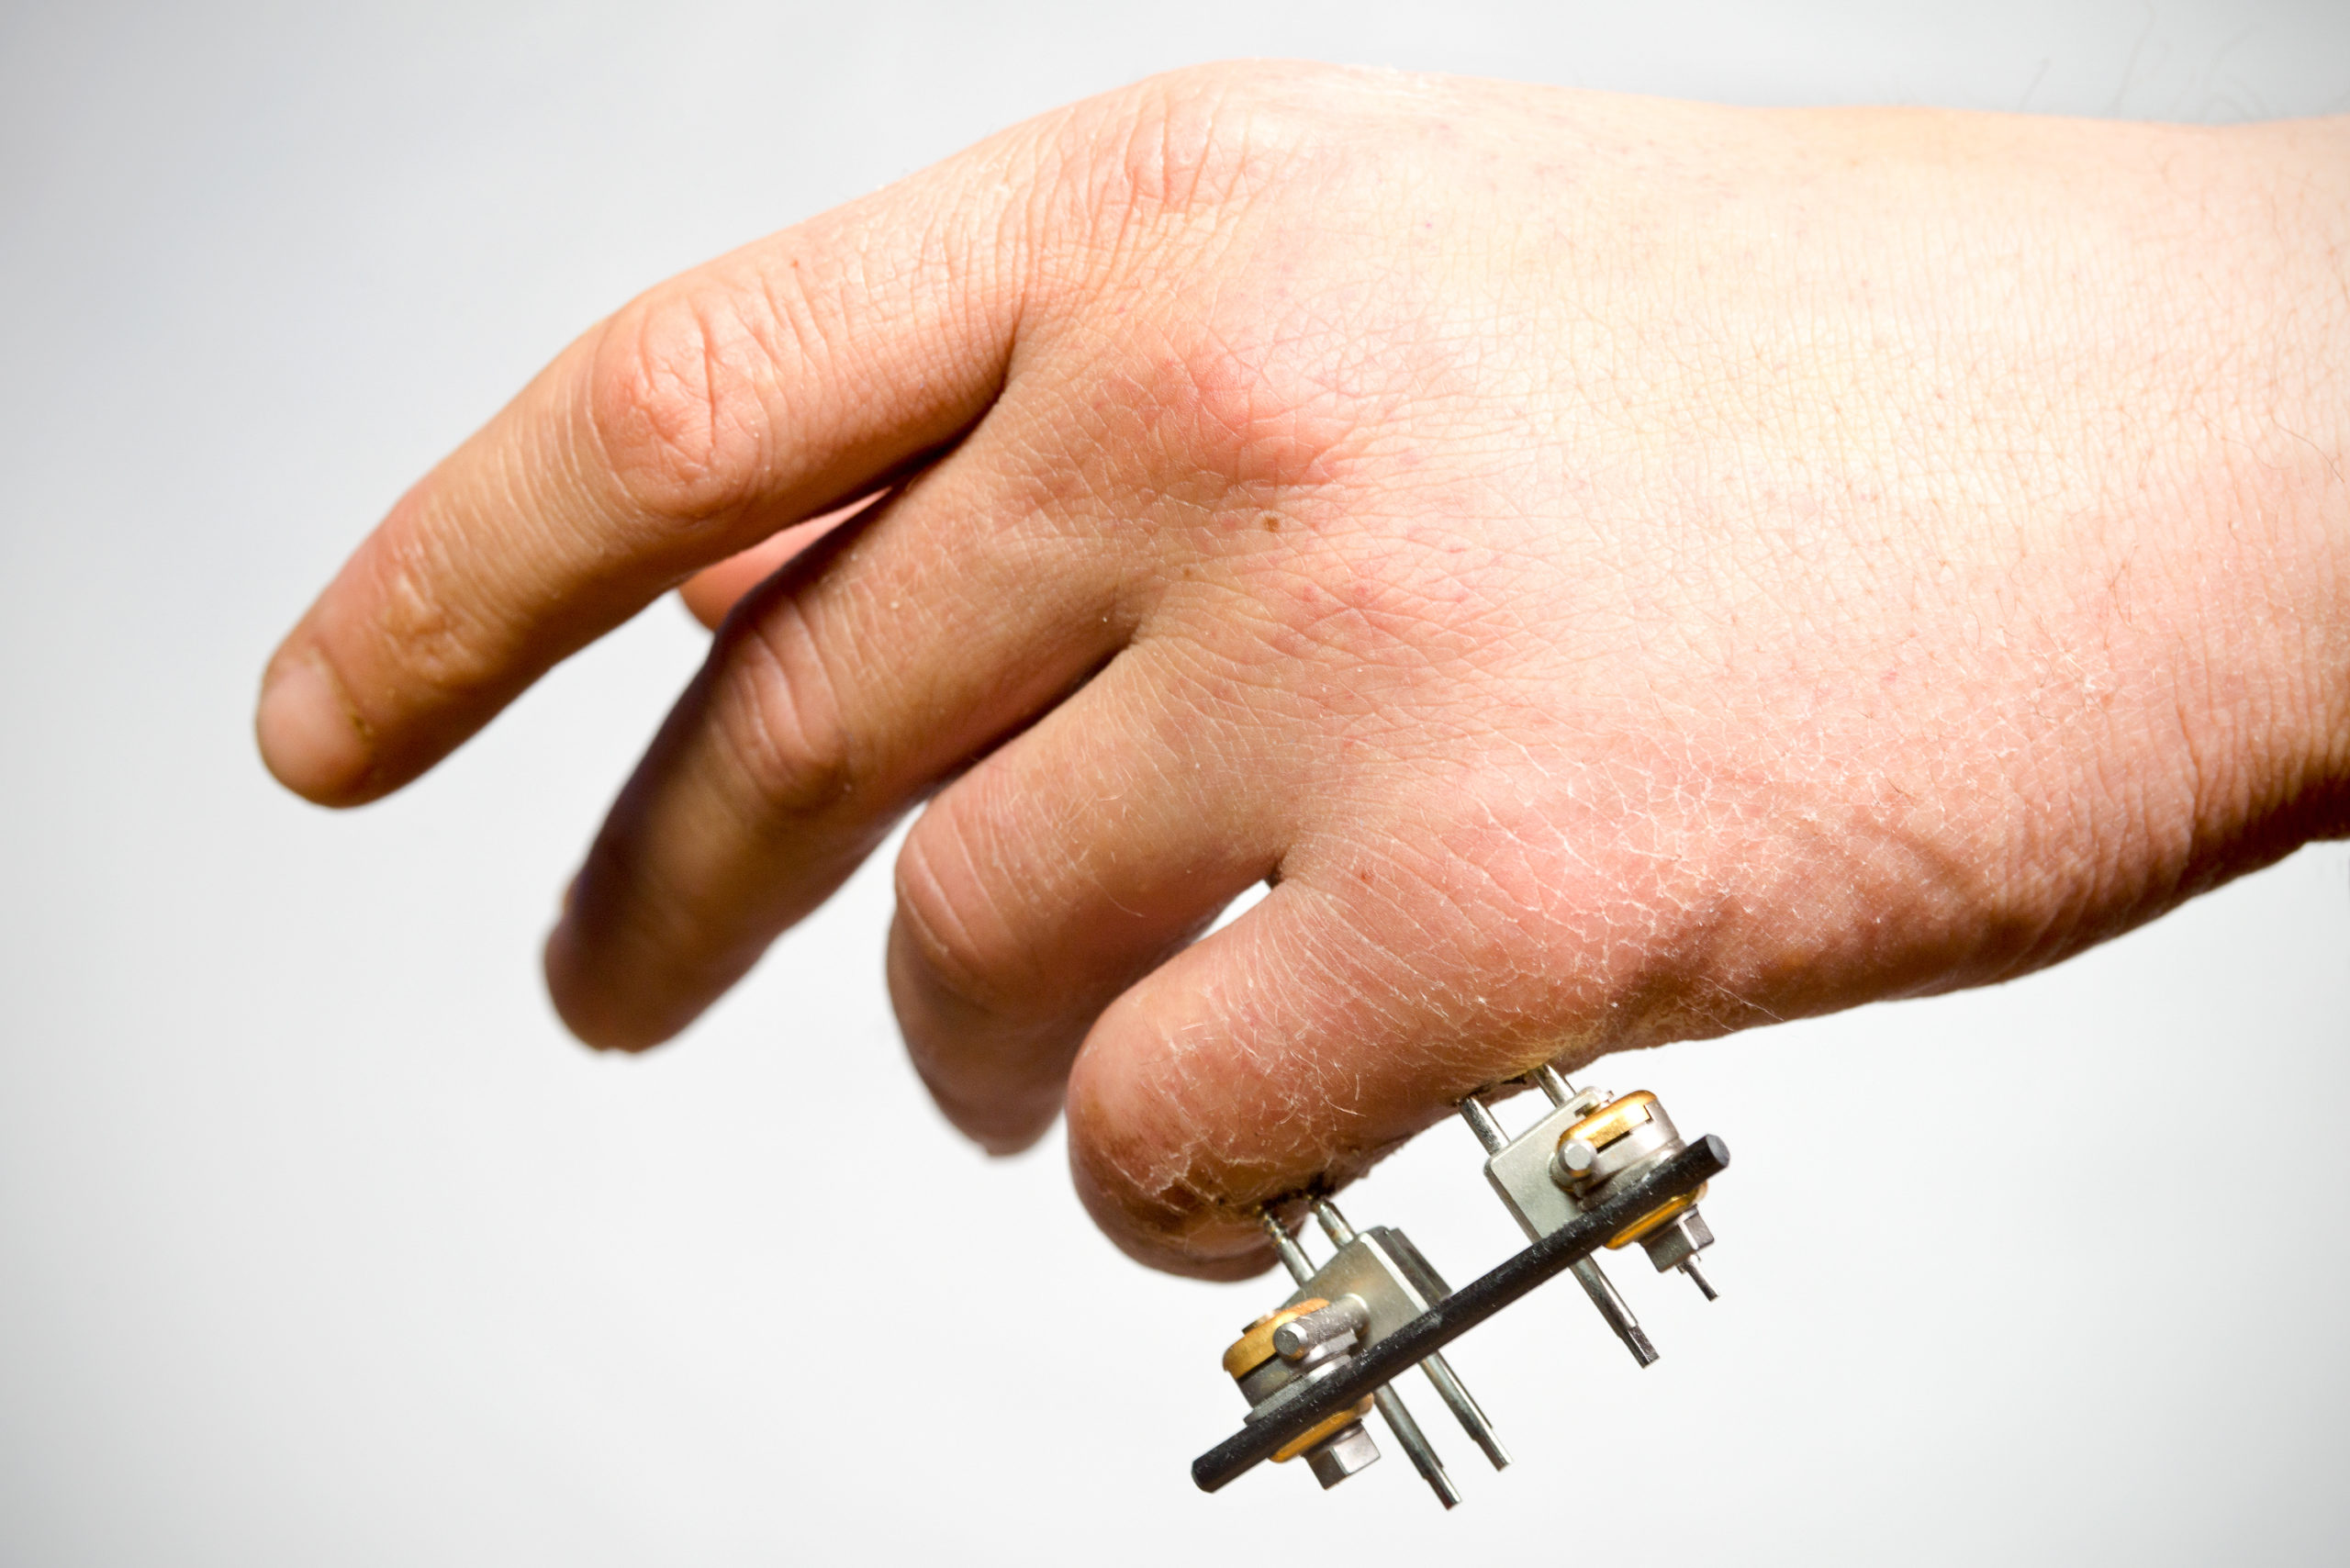

相对运动矫形器与动态伸展矫形器相比,哪种矫形器设计更适合 5-6 区伸肌腱损伤?

M. Buhler, ˝ D. Gwynne-Jones, M. Chin 等人,(2023) 与动态伸展相比,相对运动伸展矫形器的结果是否非劣质且具有成本效益......